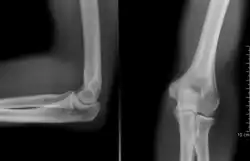

Radiografía del codo. | ||

Una radiografía (también llamada roentgenografía)[1] es una imagen registrada en una placa o película fotográfica, o de forma digital (radiología digital directa o indirecta) en una base de datos, obtenida al exponer al receptor a una fuente de radiación de alta energía, comúnmente rayos X o radiación gamma procedente de isótopos radiactivos (iridio-192, cobalto-60, cesio-137, etc.). Al interponer un objeto entre la fuente de radiación y el receptor, las partes más densas aparecen con diferentes tonos dentro de una escala de grises.